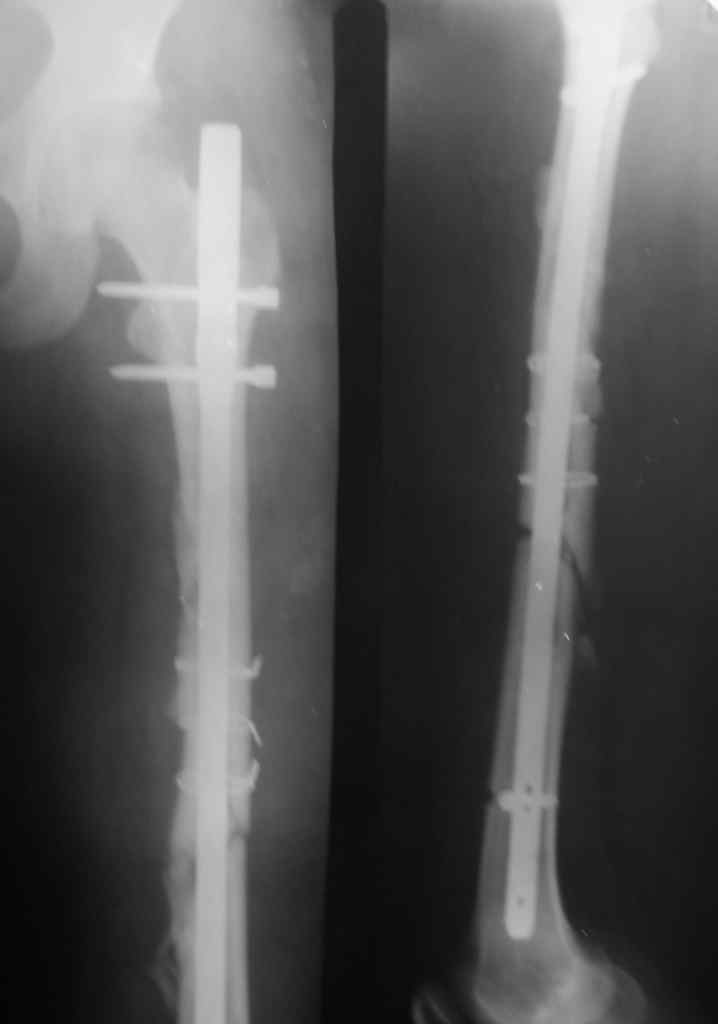

Перелом стержня, серкляж

Поступила молодая,маленькая девочка 18 лет с болями в левом бедре. Из истории:автодорожная травма в ноябре 2005 года, тогда же оперировалась данным способом. Проживает в селе и как правило в таких случаях выпала из поля зрения ведущего доктора.

По нашему мнению возможен реостеосинтез штифтом с рассверливанием более большого диаметра.Но возникают вопросы:

НА мой взгляд проблема вот в чём перелом стержня произошёл потому, что не произошло сращение перелома в обычные сроки. Отломки, которые фиксированы серкляжём практически 100 % нежизнеспособны.Наверняка их во время операции отделили от мышц и конец им. Поэтому необходимо удалить нежизнеспособные отломки вместе с серкляжной проволокой, гвоздь удалить.Поставить новый любой фирмы с блокированием с рассверливанием в область дефекта поставить металлокаркас, набить его костной крошкой и ждать перестройки костной ткани в металлокаркасе.Гвоздь будет удержировать длинну и ось ,а каркас сам по себе неплохо зажимается в условиях компрессии и создаст условия для перестройки трансплантата. А.Семенистый показывал на прошлой неделе плечо посмотрите.Принцип тот же. С уважением

По сути, получился остеосинтез пластиной - статическое запирание вкупе с обнажением для серкляжа.